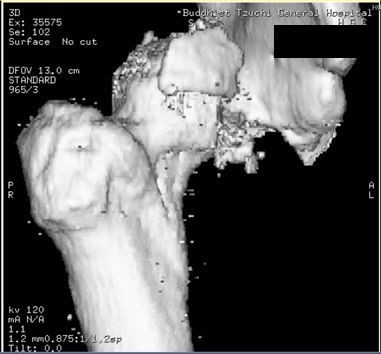

圖:從電腦斷層檢查中,看見洪先生右大腿股骨因為強力撞擊,已經穿出髖關節。

而當時的主治醫師就是個性直率低調,被同事與後進同仁暱稱為鄺爺的骨科鄺世通醫師,這個在鄺醫師口中的小骨折,其實是包含髖關節、大腿股骨、膝蓋髕骨、與小腿脛骨等多處粉碎性骨折的複雜個案,不論是X光檢查,還是電腦斷層檢查,都能看見因為強力撞擊穿出髖關節的股骨,還有粉碎的髕骨,歷經數個小時的開刀,才救回洪國程先生的性命與右腿。